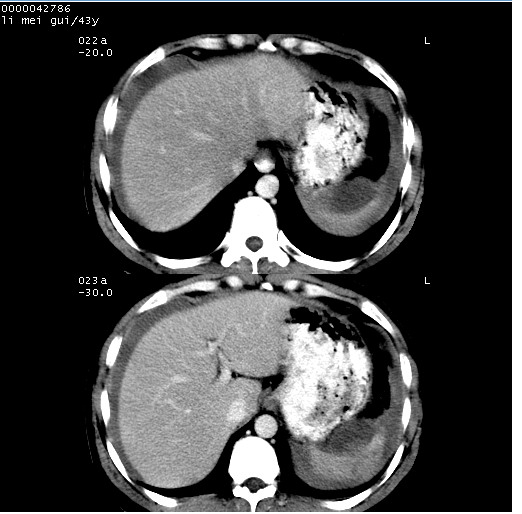

| 患者,男,43岁。突发腹痛2小时,面色苍白,难以平卧。自述近期无明确外伤史,为摩托车驾驶员。 腹部b超检查:脾脏中上极回声异常,肿瘤待排。 临床诊断:腹痛原因待查。 上中腹部ct轴位平扫+增强扫描(层厚10mm,螺距1.0,重建间隔10mm),图像如下: ![]() ![]() ![]() ![]() ![]() ![]() ![]() ![]() ![]() ![]() ![]() ![]() ![]() ![]() ![]() ![]() ![]() ![]() ![]() ![]() ![]() ![]() ![]() ![]() ![]() ![]() ![]() ![]() ![]() ![]() ![]() ![]() ![]() ![]() ![]() zrs发言:支持脾破裂 wwp发言:支持脾破裂并腹水。 xulianj发言:脾脏肿瘤破裂可能性大 zsl6918发言:不像肿瘤出血,考虑还是与外伤后引起的慢性出血有关 zzyy发言:平扫见肝周及脾周积液,脾内密度不均。脾内肿瘤较少见。还是外伤性脾破裂。 沈丘东方医院发言:脾门区一个不均匀强化病灶与其周液体相连多考虑脾占位破裂出血 yixianman001011发言:脾破裂并腹水是可以肯定的,具体原因多以肿瘤性破裂出血,脾脏淋巴瘤可能性大. 结果: 术后,经详细询问患者,其仔细回忆:一月前骑摩托时左侧腰部与别人有“轻微”触碰,因责任在自已,当时又无明显不适,未引起注意。 临床术后诊断:脾破裂并失血性休克(1.外伤性迟发性脾破裂。2.脾脏肿瘤破裂?) 术后标本病检:脾破裂并出血,未见明显肿瘤成份。 原贴地址:http://www.radinet.com.cn/forum_view.asp?forum_id=4&view_id=34070 |